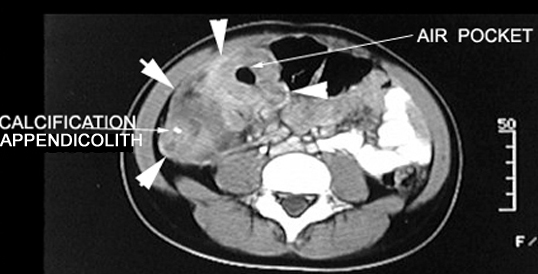

Acute Appendicitis Appendiceal abscess

CT Post Contrast:

• Arrrows point to the inflammatory mass in the right lower quadrant with an air pocket indicating an abscess.

• Mass demonstrates contrast enhancement.

• Calcification seen within the mass probably represents an appendicolith.